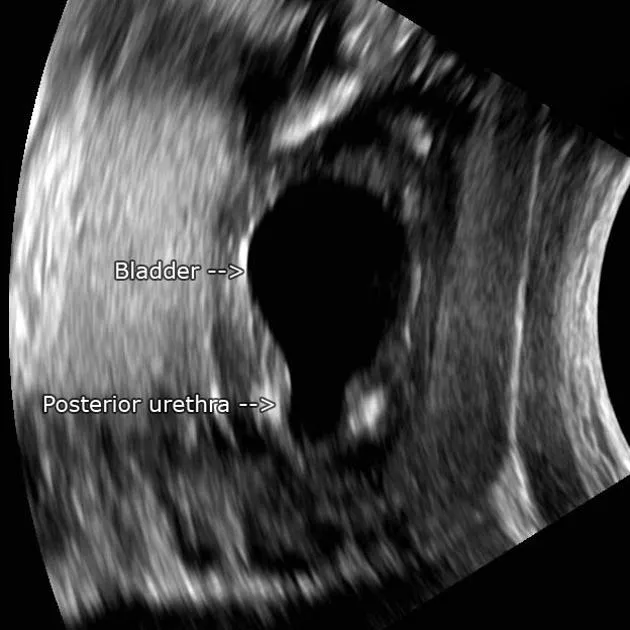

Posterior Urethral Valves (PUV): Obstructing membranes in the posterior male urethra; the most common cause of bladder outlet obstruction in male infants.

- Dx: VCUG. Antenatal ultrasound may show a "keyhole sign" (dilated bladder + posterior urethra).

⭐ In PUV, the "keyhole sign" on antenatal ultrasound is a classic finding, representing a dilated bladder and posterior urethra.

- Posterior Urethral Valves (PUV): #1 cause of congenital bladder outlet obstruction in males; see 'keyhole' sign on USG.